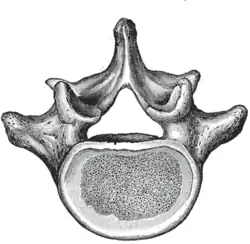

The adjacent figure depicts the general characteristics of the first through fourth lumbar vertebrae. The fifth vertebra contains certain peculiarities, which are detailed below.

As with other vertebrae, each lumbar vertebra consists of a vertebral body and a vertebral arch. The vertebral arch, consisting of a pair of pedicles and a pair of laminae, encloses the vertebral foramen (opening) and supports seven processes.

Body

The vertebral body of each lumbar vertebra is kidney shaped, wider from side to side than from front to back, and a little thicker in front than in back. It is flattened or slightly concave above and below, concave behind, and deeply constricted in front and at the sides.[1]

Arch

The pedicles are very strong, directed backward from the upper part of the vertebral body; consequently, the inferior vertebral notches are of considerable depth.[1] The pedicles change in morphology from the upper lumbar to the lower lumbar. They increase in sagittal width from 9 mm to up to 18 mm at L5. They increase in angulation in the axial plane from 10 degrees to 20 degrees by L5. The pedicle is sometimes used as a portal of entrance into the vertebral body for fixation with pedicle screws or for placement of bone cement as with kyphoplasty or vertebroplasty.

The laminae are broad, short, and strong.[1] They form the posterior portion of the vertebral arch. In the upper lumbar region the lamina are taller than wide, but in the lower lumbar vertebra the lamina are wider than tall. The lamina connects the spinous process to the pedicles.

The vertebral foramen within the arch is triangular, larger than the thoracic vertebrae, but smaller than in the cervical vertebrae.[1]

Processes

The spinous process is thick, broad, and somewhat quadrilateral; it projects backward and ends in a rough, uneven border, thickest below where it is occasionally notched.[1]

The superior and inferior articular processes are well-defined, projecting respectively upward and downward from the junctions of pedicles and laminae. The facets on the superior processes are concave, and look backward and medialward; those on the inferior are convex, and are directed forward and lateralward. The former are wider apart than the latter since in the articulated column, the inferior articular processes are embraced by the superior processes of the subjacent vertebra.[1]

The transverse processes are long and slender. They are horizontal in the upper three lumbar vertebrae and incline a little upward in the lower two. In the upper three vertebrae they arise from the junctions of the pedicles and laminae, but in the lower two they are set further forward and spring from the pedicles and posterior parts of the vertebral bodies. They are situated in front of the articular processes instead of behind them as in the thoracic vertebrae, and are homologous with the ribs.[1]

Three portions or tubercles can be noticed in a transverse process of a lower lumbar vertebrae: the lateral or costiform process, the mammillary process, and the accessory process.[2] The costiform is lateral, the mammillary is superior (cranial), and the accessory is inferior (caudal). The mammillary is connected in the lumbar region with the back part of the superior articular process. The accessory process is situated at the back part of the base of the transverse process. The tallest and thickest costiform process is usually that of L5.[2]